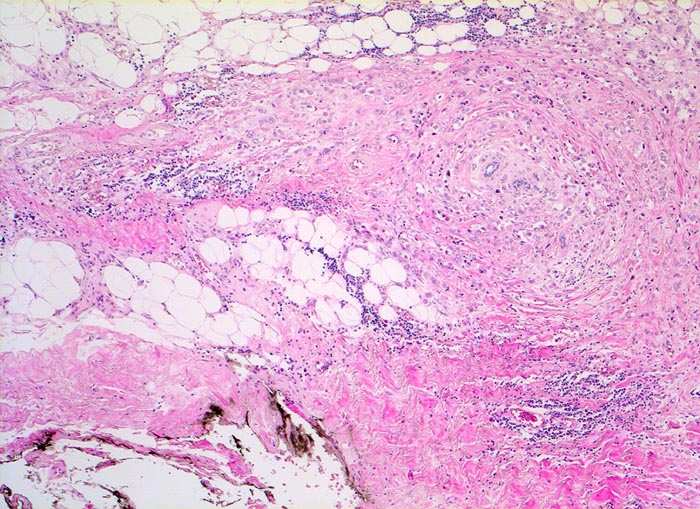

Invasives lobuläres Mammakarzinom

Die Tumorzellen sind konzentrisch um vorbestehende Läppchen angeordnet. Der Tumor reicht hier bis nahe an den mit schwarzer Tusche markierten Resektionsrand heran.

Mammographisch suspekter Herd im äusseren oberen Quadranten. Probeexzision.

Damit der Pathologe den Abstand des Tumors von den verschiedenen Resektionsrändern bestimmen kann, werden diese mit verschieden farbiger Tusche markiert